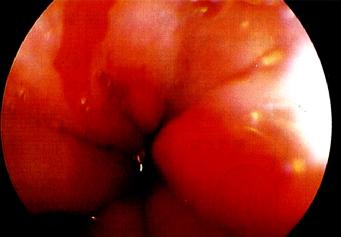

2.食管鏡檢查

典型的Barrett食管是在胃食管交界上方出現(xiàn)紅色的柱狀上皮區(qū),部分患者可見(jiàn)反流性食管損傷的征象?;顧z可證實(shí)并找到柱狀上皮化生。